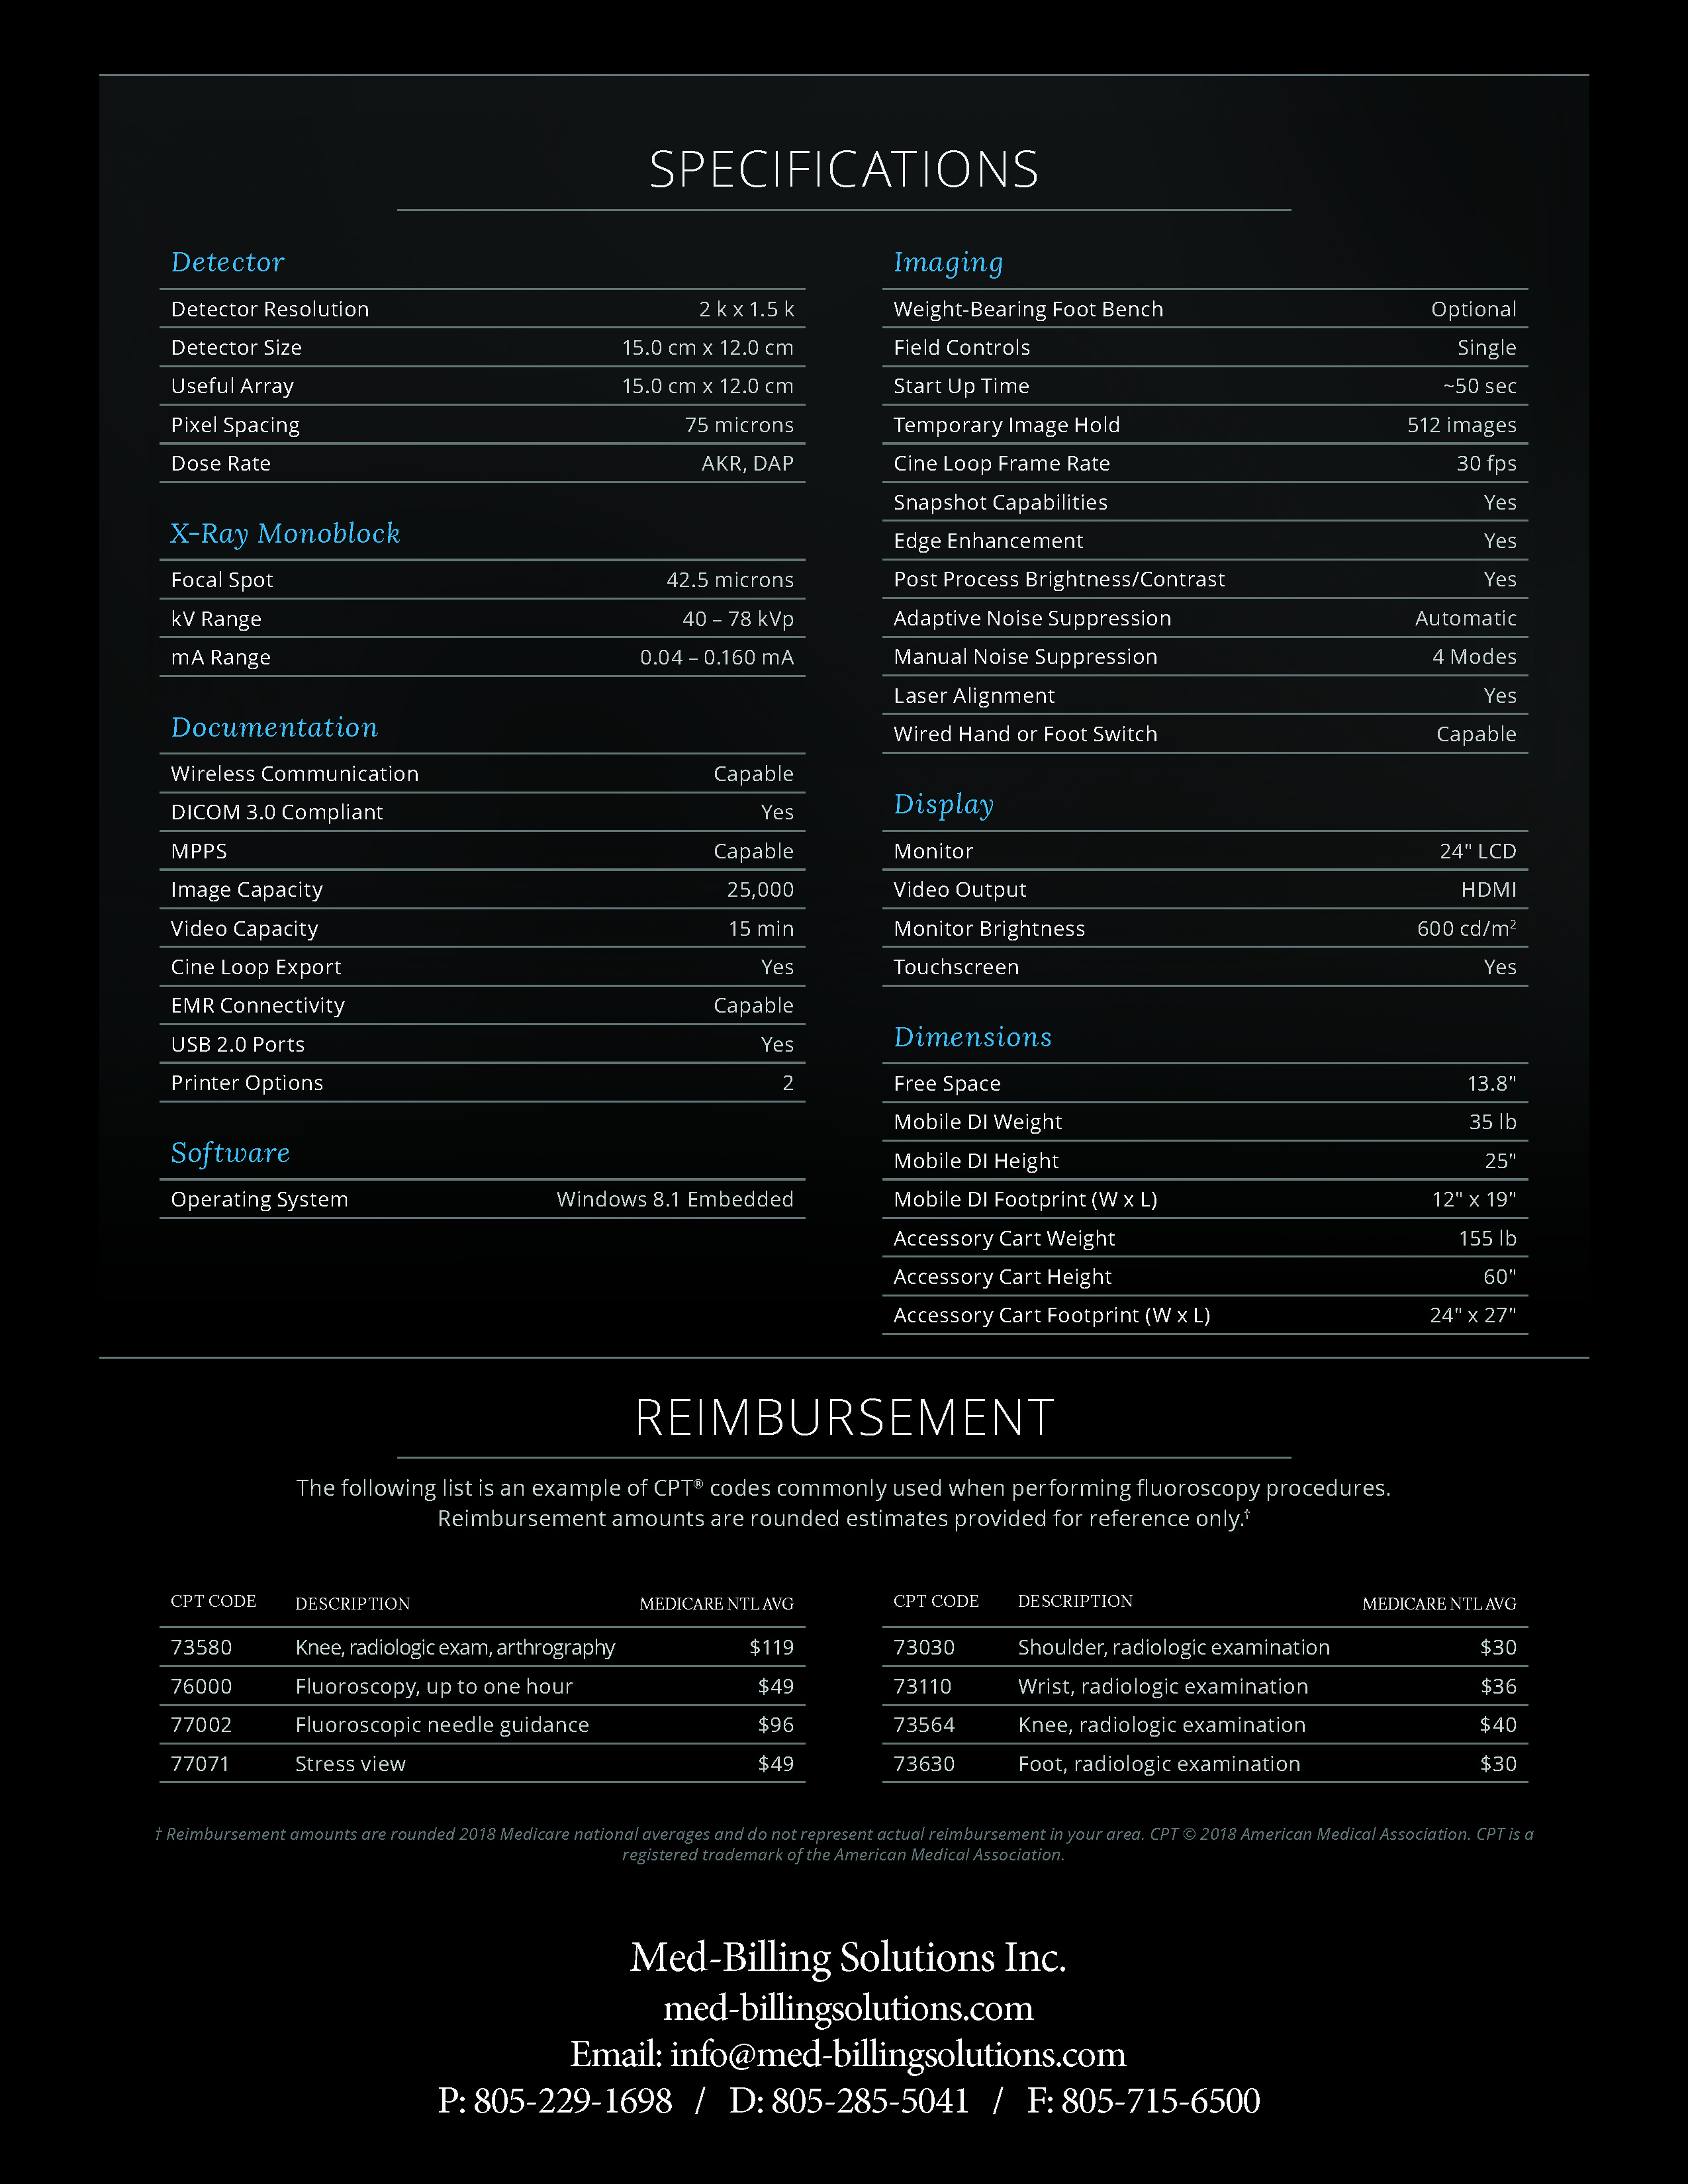

The Advanced Arthritis Relief Program (AARP) is a knee osteoarthritis (OA) treatment system that consists of fluoroscopic guided injections of Hyaluronic Acid, targeted Physical Therapy, and a special uploading Knee Brace. It’s MD, MP, and PA approved and covered by all major insurance carriers as well as Medicare.

INSURANCE CPT CODE UPDATE

2019 Fee Schedule & Coding Determination changes Osteoarthritis Joint Treatment & Pain Relief. After Standard of care for knee OA, MEDICARE requires patients try and fail viscosupplementation therapy prior to approving total knee arthroplasty (TKA). The AARP is this type of therapy that is approved by Medicare. It combines viscosupplementation with physical therapy and a specialized knee bracing procedure that has been delivering near perfect results.

2019 Fee Schedule & Coding Determination changes Osteoarthritis Joint Treatment & Pain Relief. After Standard of care for knee OA, MEDICARE requires patients try and fail viscosupplementation therapy prior to approving total knee arthroplasty (TKA). The AARP is this type of therapy that is approved by Medicare. It combines viscosupplementation with physical therapy and a specialized knee bracing procedure that has been delivering near perfect results.